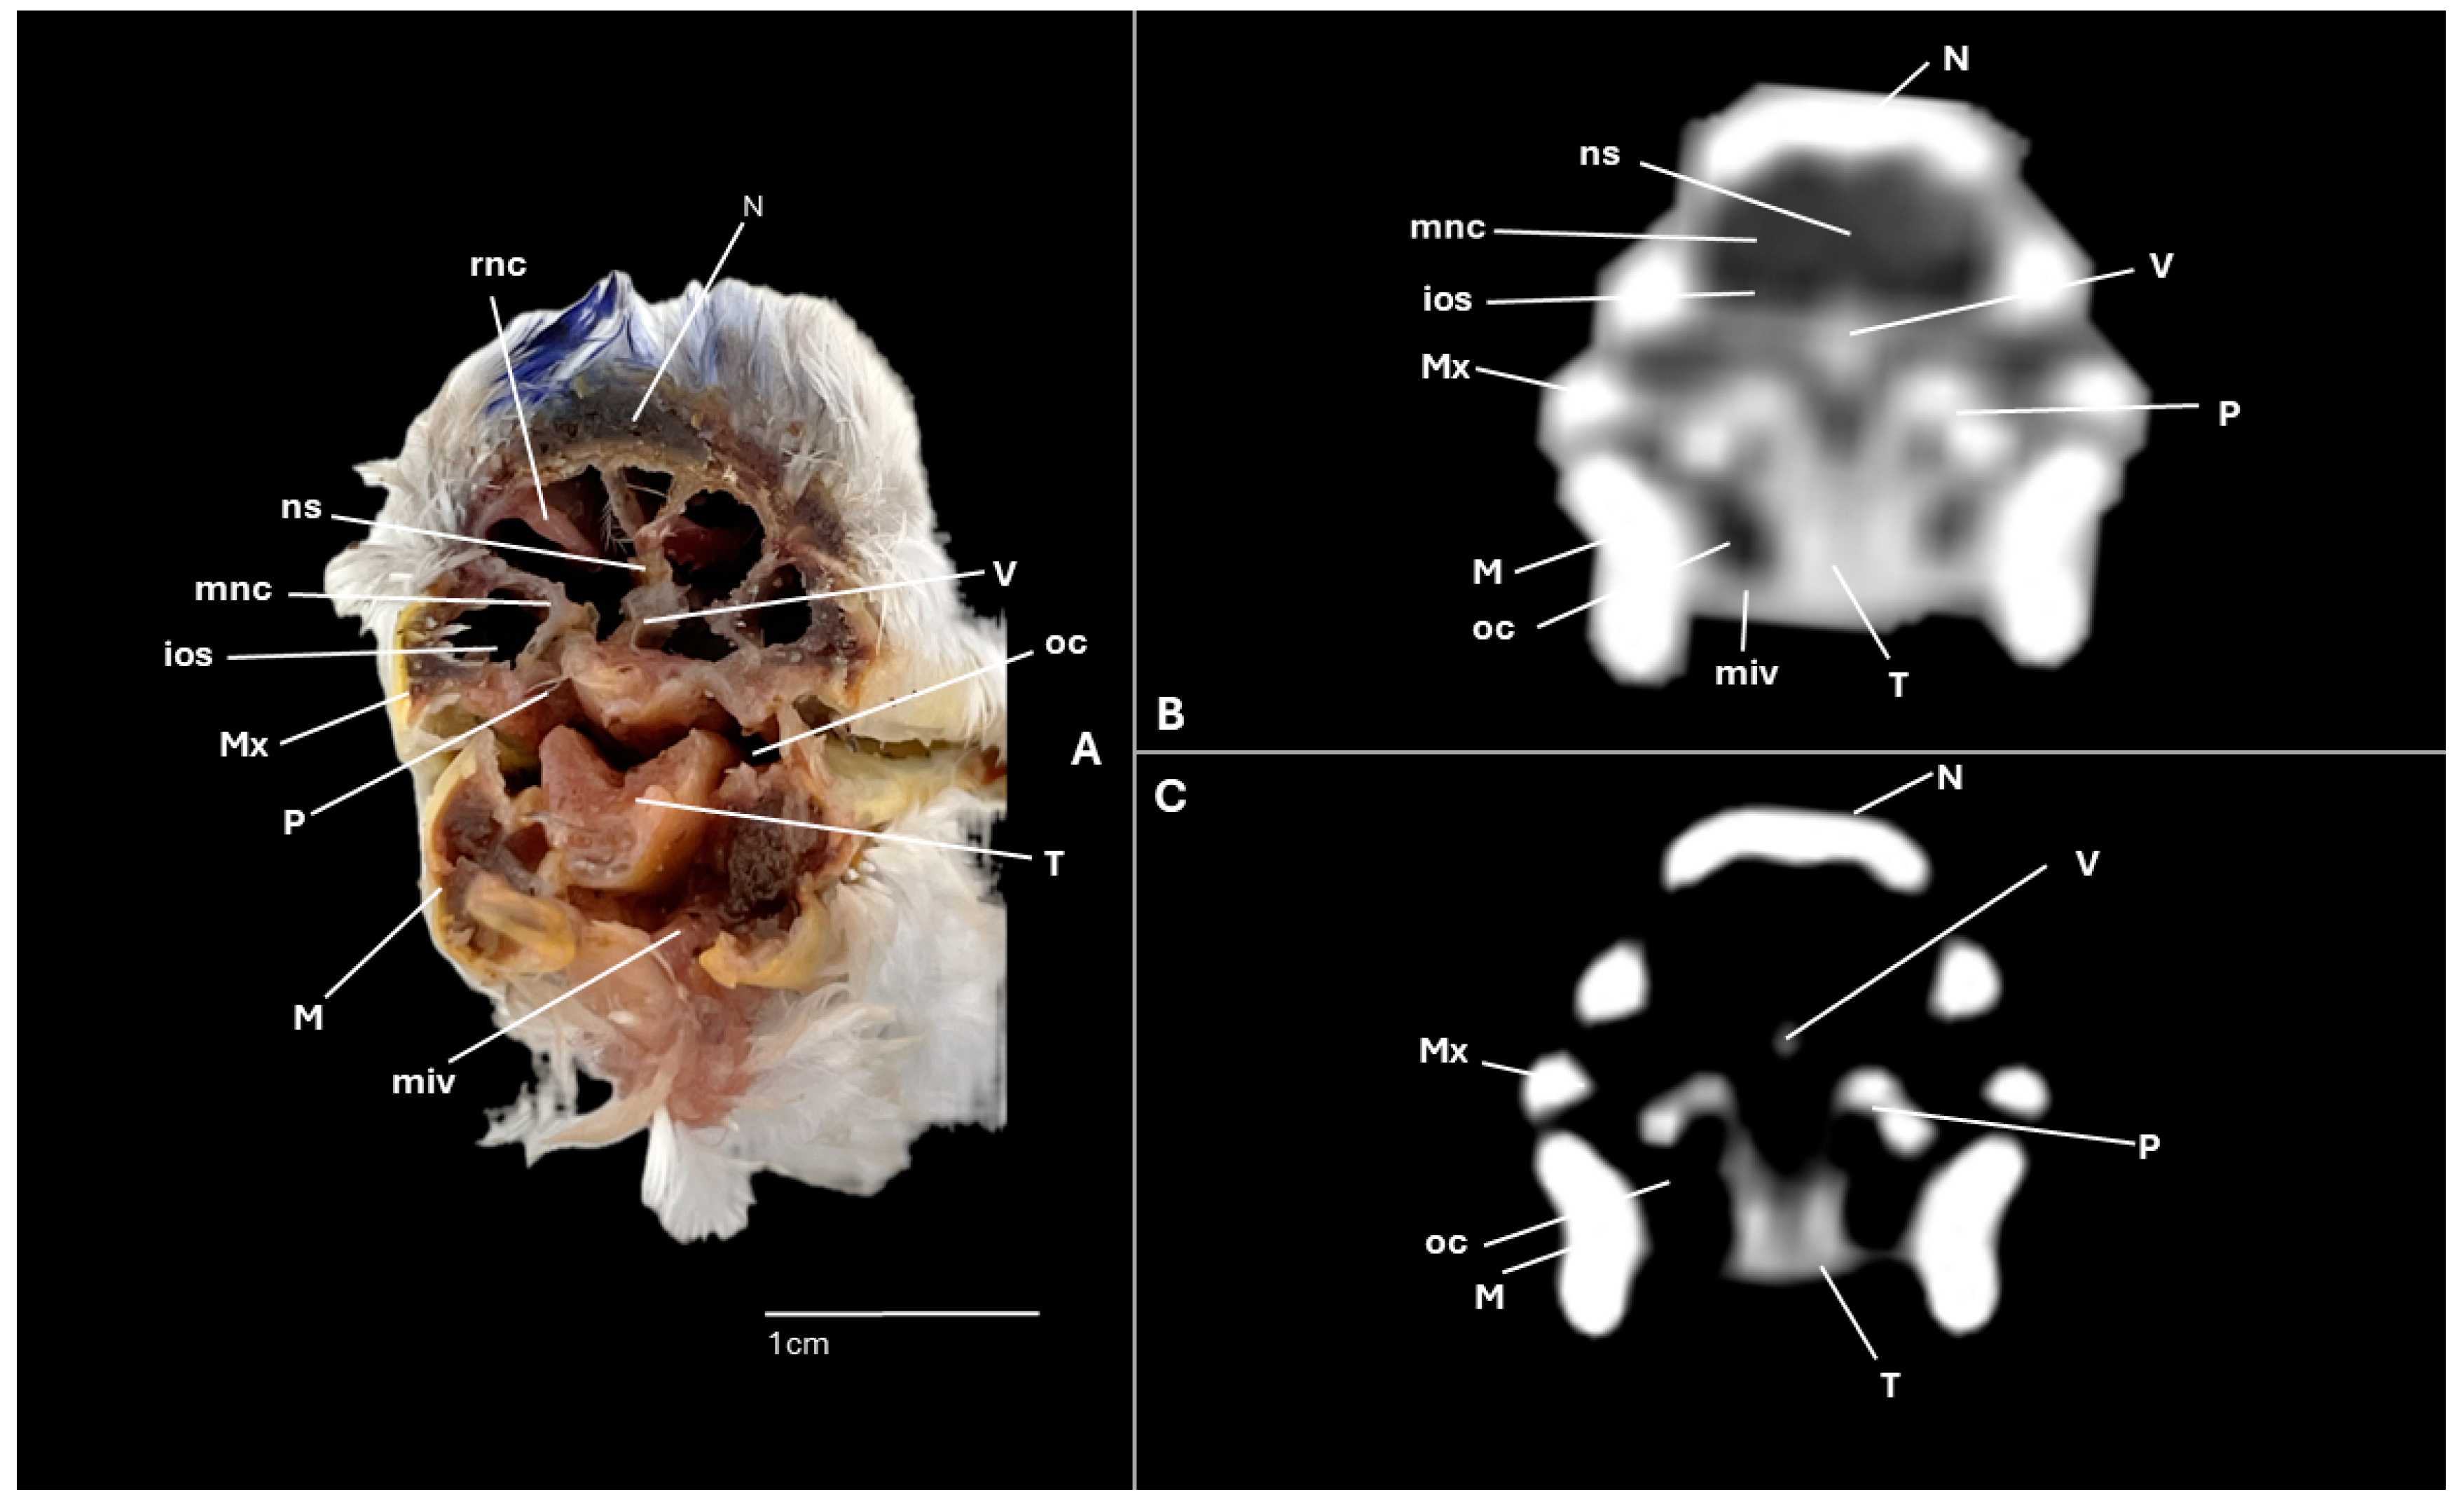

3.1. Anatomical Cross-Sections

3.2. Computed Tomography (CT)